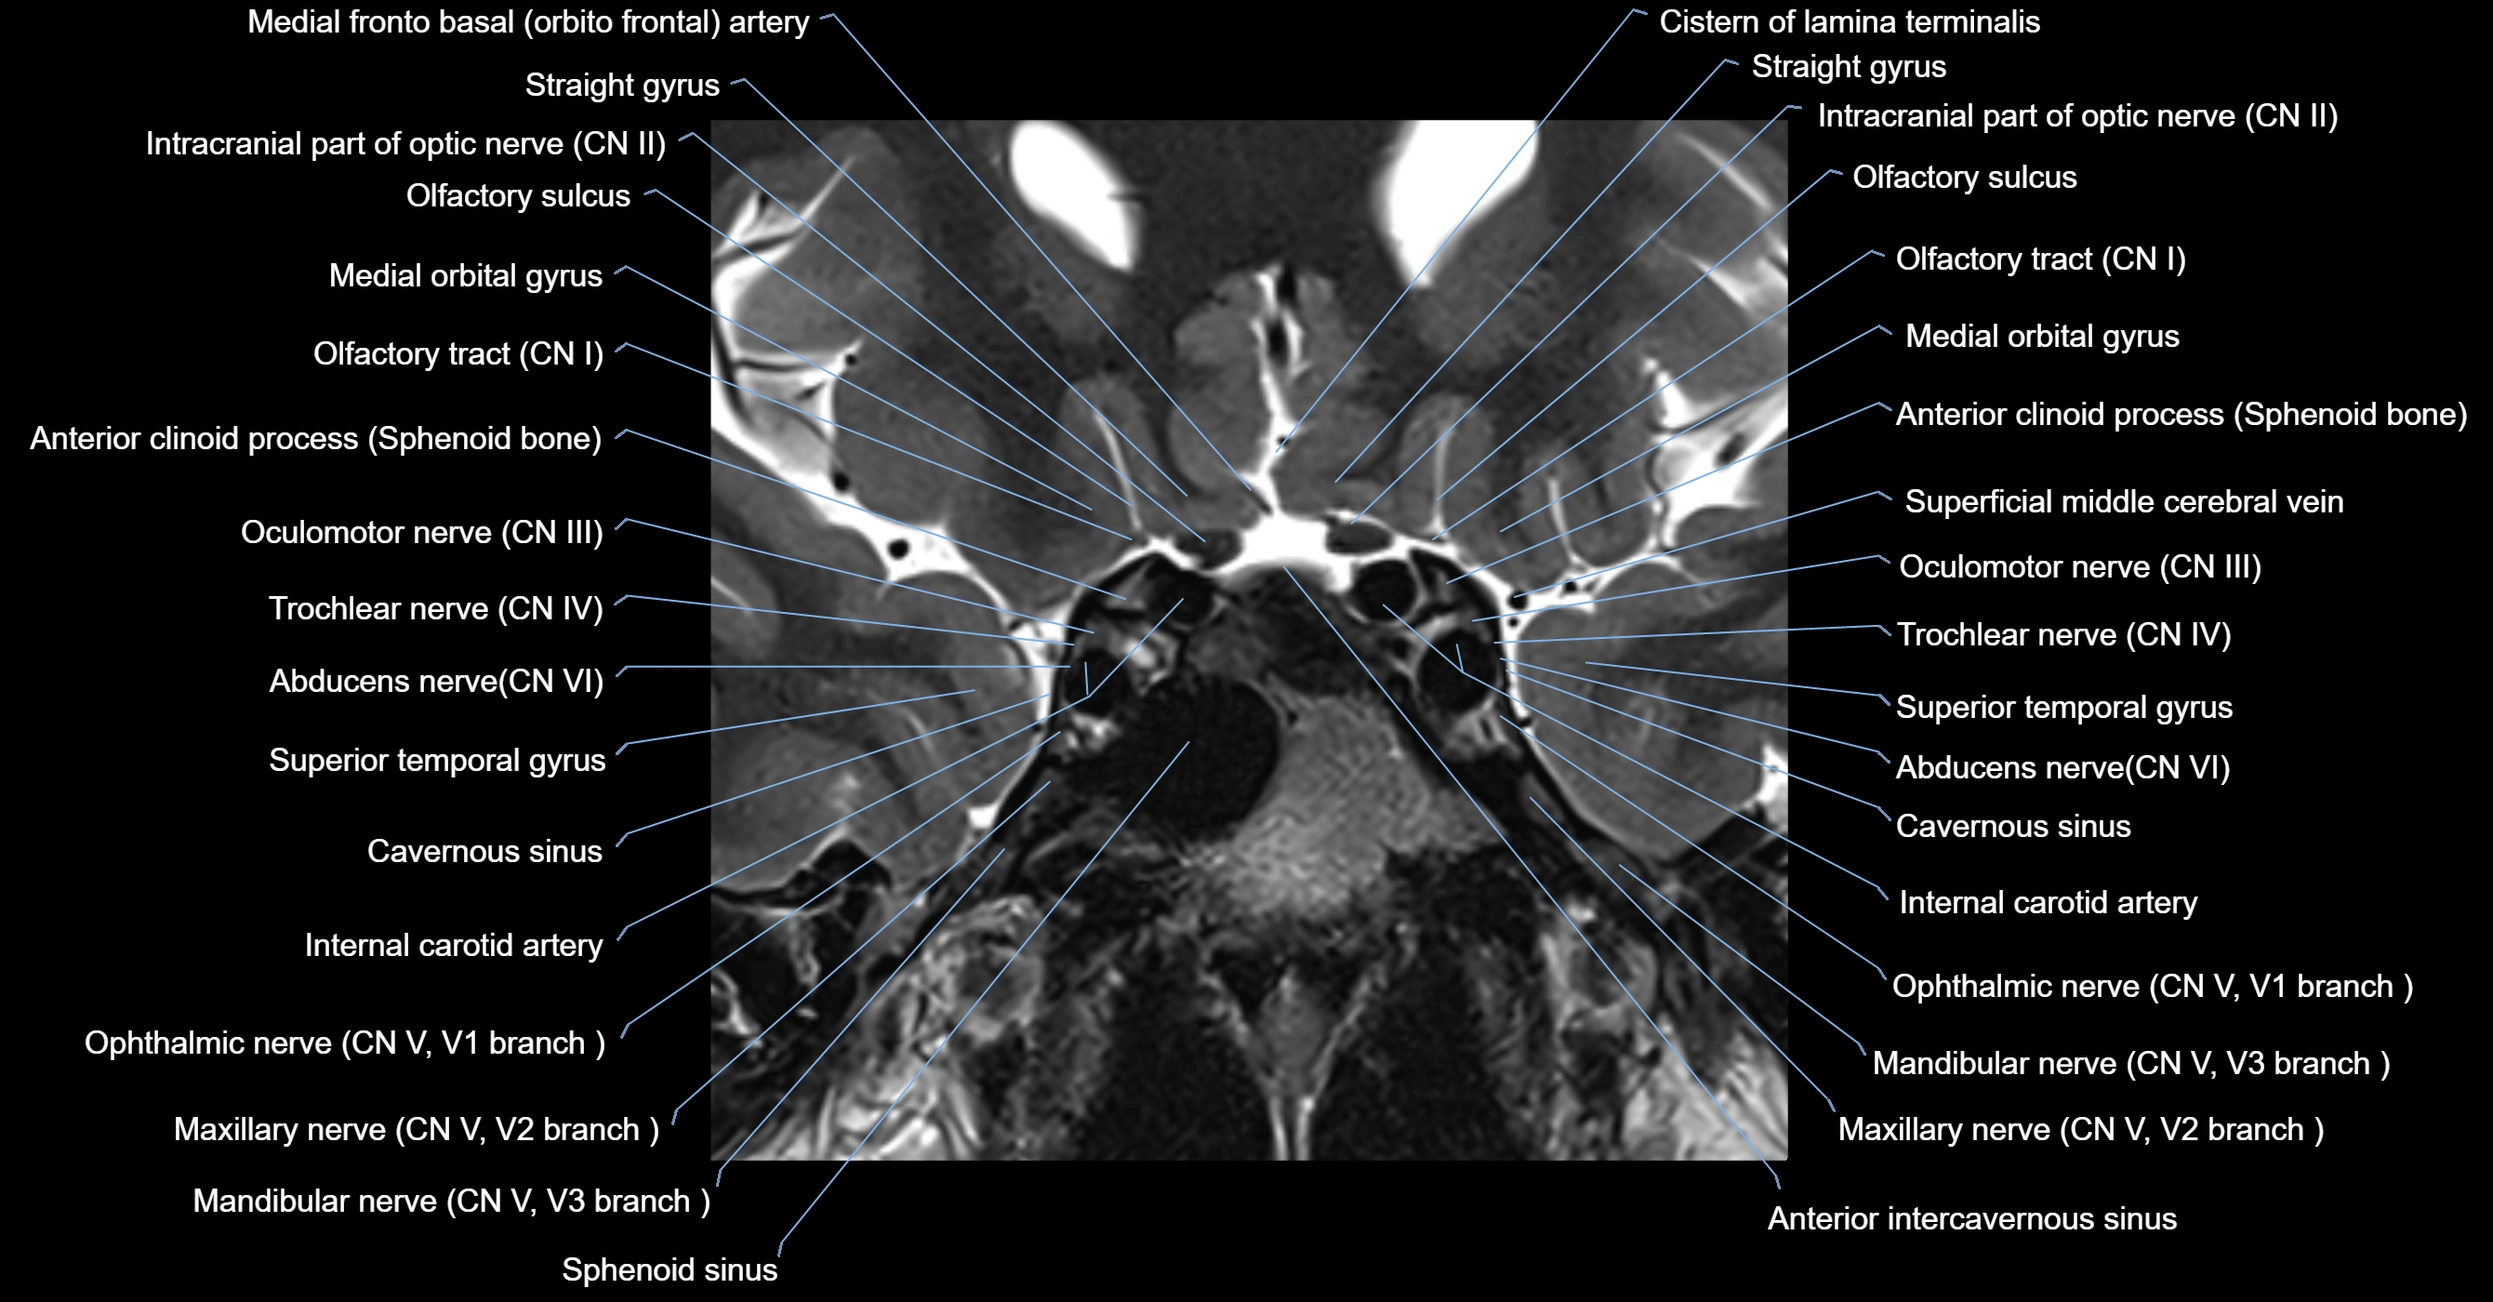

MRI Appearance

-

The abducens nerve is a small, thin, linear structure

Best visualized on high-resolution T2-weighted 3D MRI sequences (e.g., FIESTA or CISS)

Seen as a hypointense (dark) line running from the brainstem at the pontomedullary junction, traversing the prepontine cistern, and entering Dorello’s canal under the petrosphenoidal ligament, then into the cavernous sinus, and finally the orbit

May be challenging to visualize in standard MRI due to its small size

Pathology may be inferred by absence, displacement, or enhancement of the nerve

MRI images